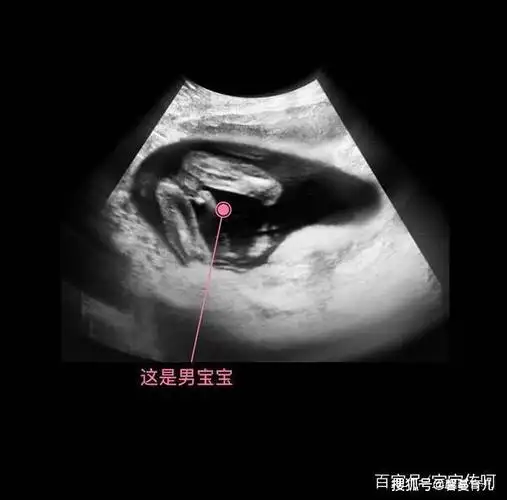

孕 周二维超声示胎儿男性外生殖器,呈「郁金香征」

广州妈妈告诉你两张b超图片便可提前知道是男是女